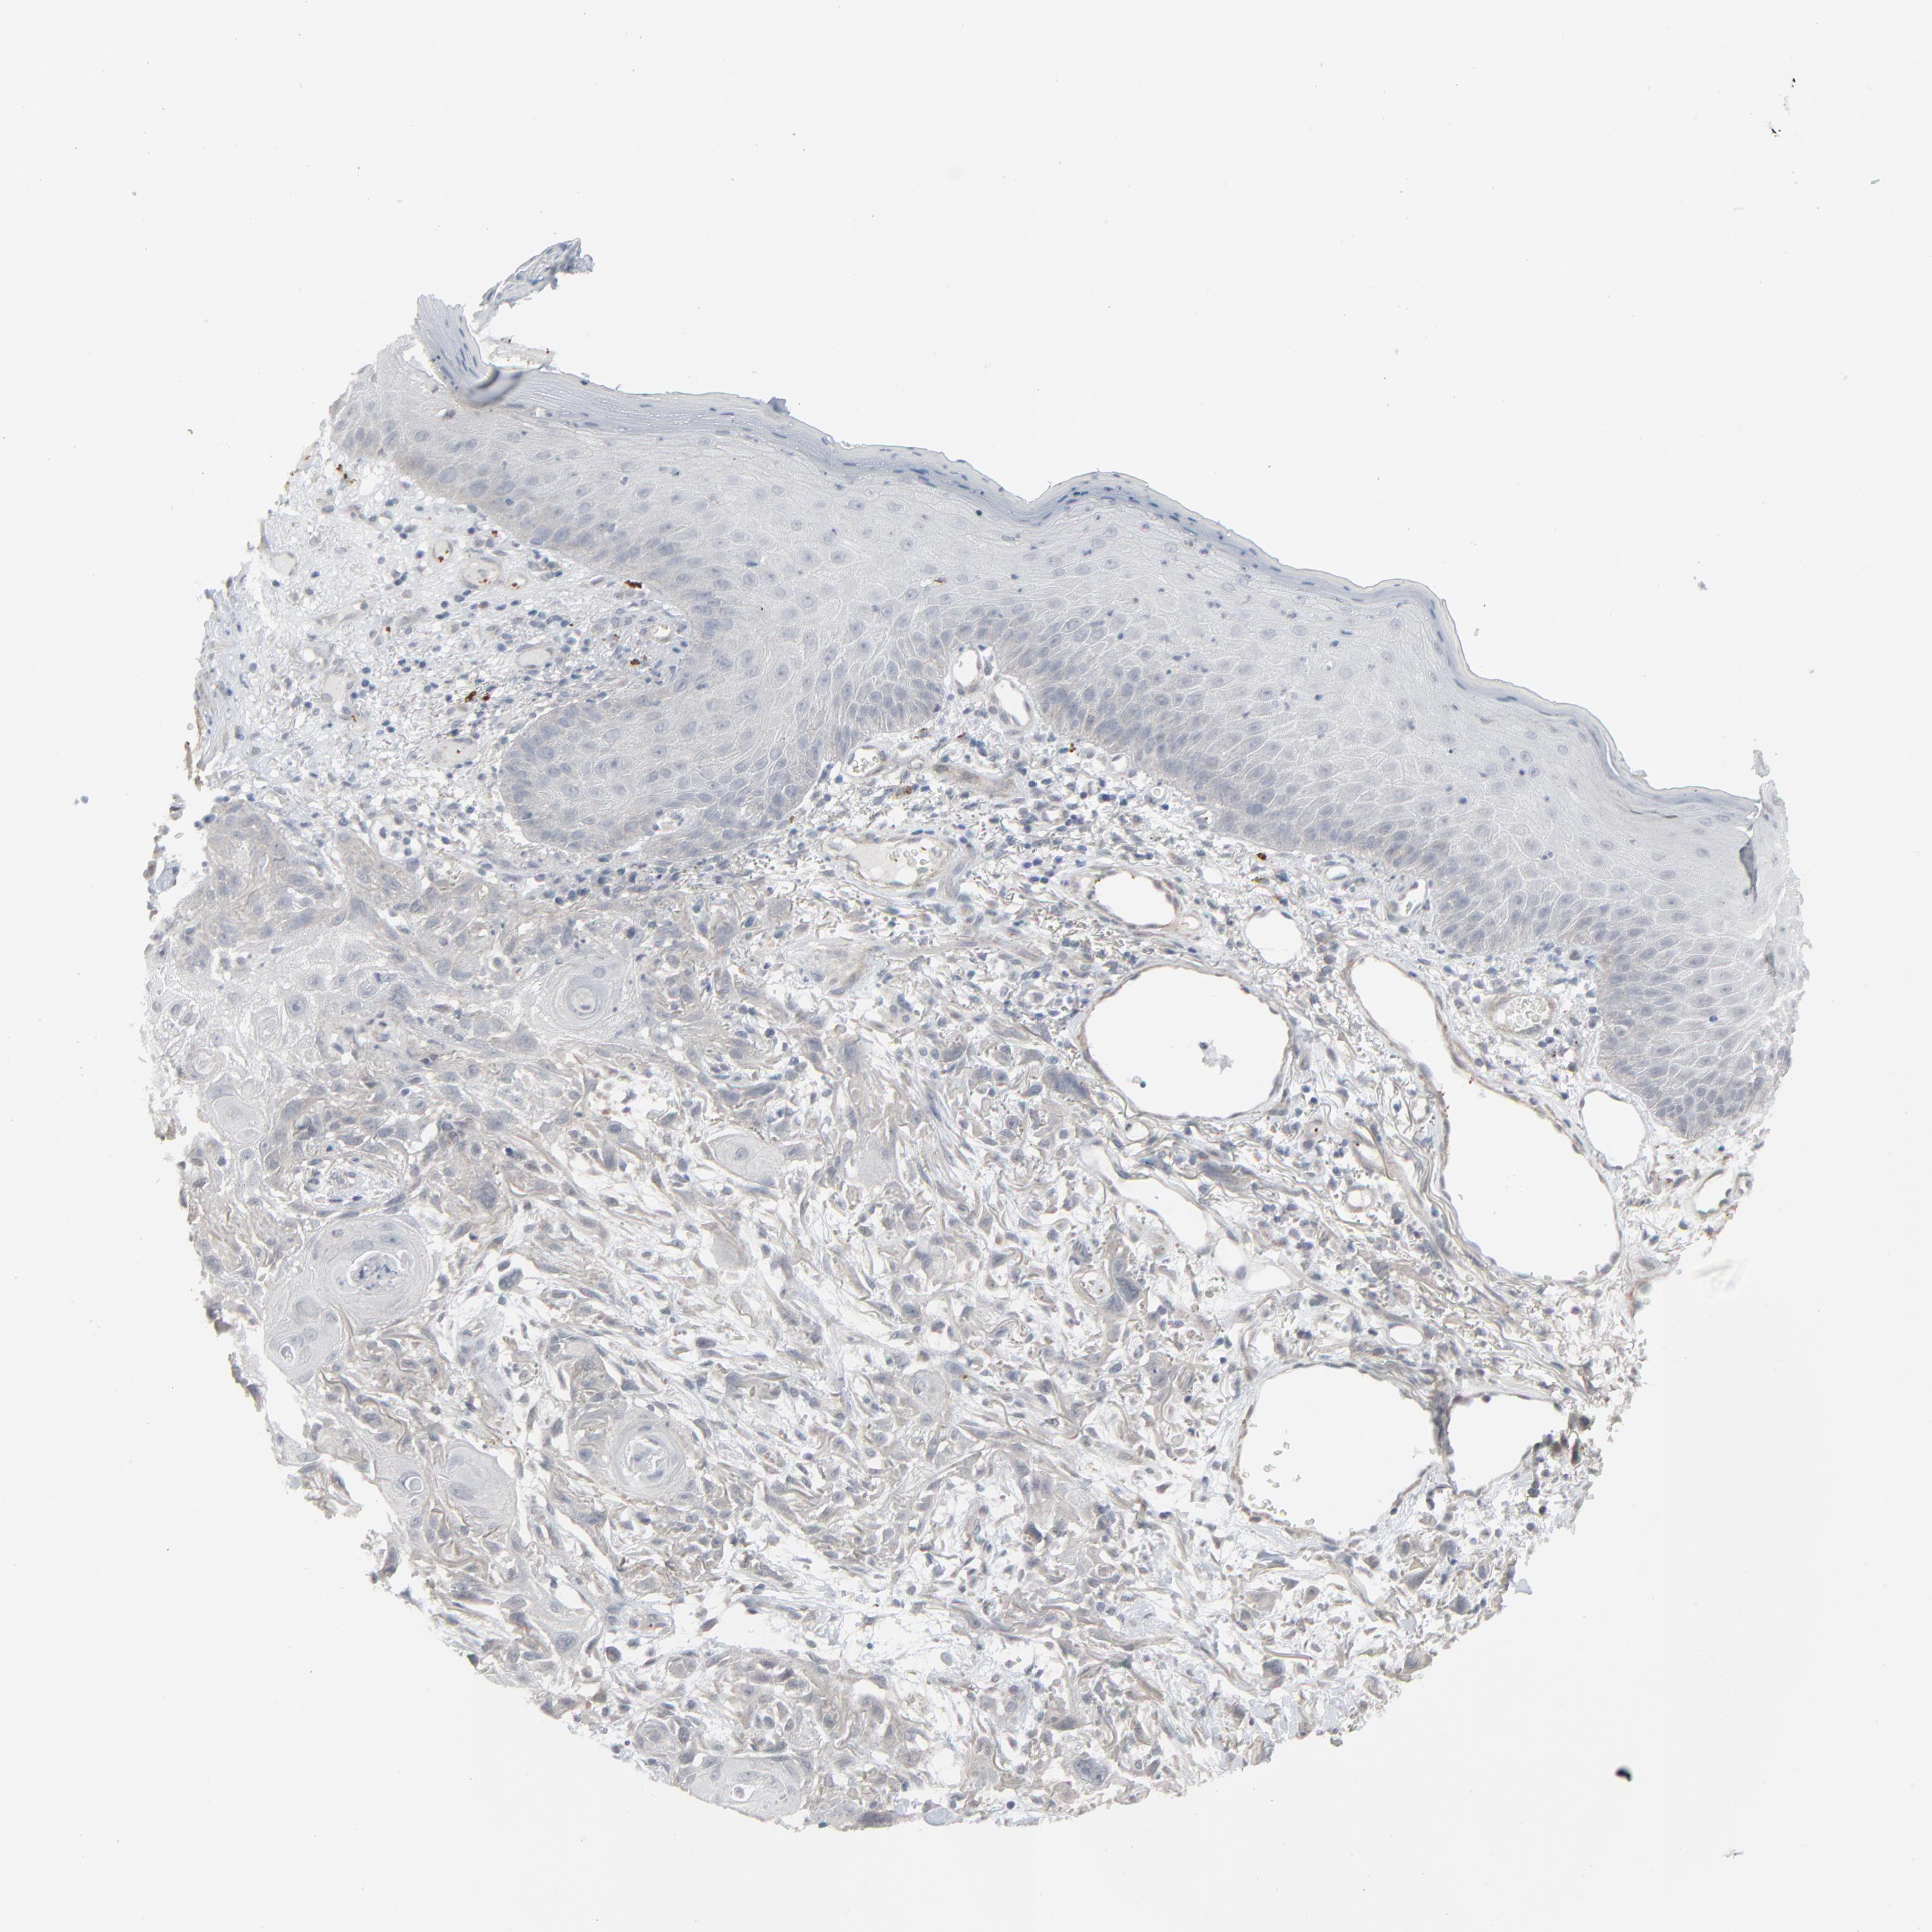

SKIN CANCER - Protein expressioni

A mouse-over function shows sample information and annotation data. Click on an image to view it in a full screen mode. Samples can be filtered based on level of antibody staining by selecting one or several of the following categories: high, medium, low and not detected. The assay and annotation is described here.

Antibody stainingi

Antibody staining in the annotated cell types in the current human tissue is reported as not detected, low, medium, or high, based on conventional immunohistochemistry profiling in selected tissues. This score is based on the combination of the staining intensity and fraction of stained cells.

Each image is clickable and will lead to virtual microscopy that enables deeper exploration of all samples and also displays staining intensity scores, fraction scores and subcellular localization as well as patient and tissue information for each sample.

Antibody HPA003278

Antibody CAB022450

Squamous cell carcinoma, NOS

Basal cell carcinoma